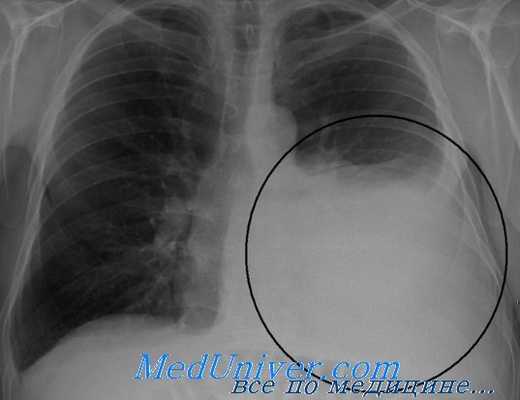

Рентгенограмма при гемотораксе